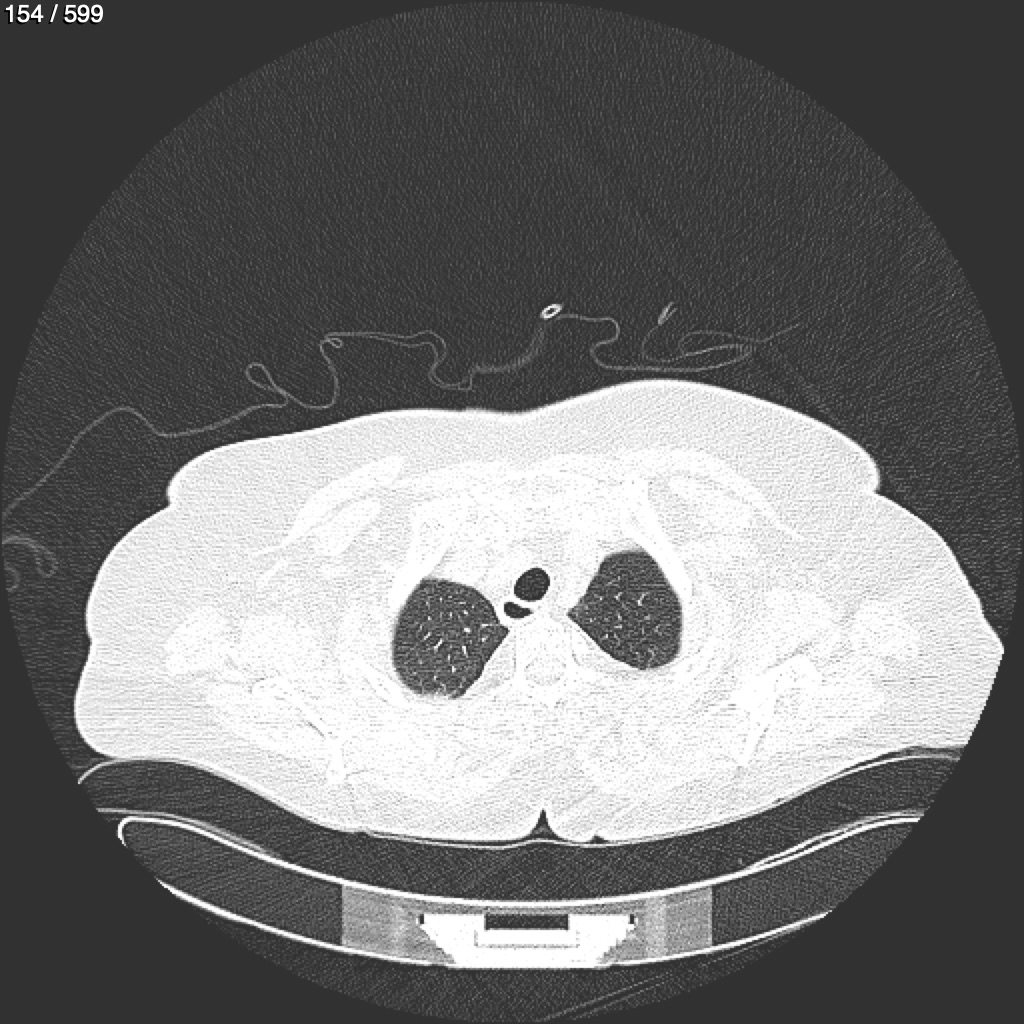

Home G​l​o​r​i​a​ ​G​l​a​d​y​s​ ​B​e​a​s​l​e​y​ ​-​ ​T​ó​r​a​x​ ​T​o​r​a​x​_​S​i​m​p​l​e​ ​(​A​d​u​l​t​o​)